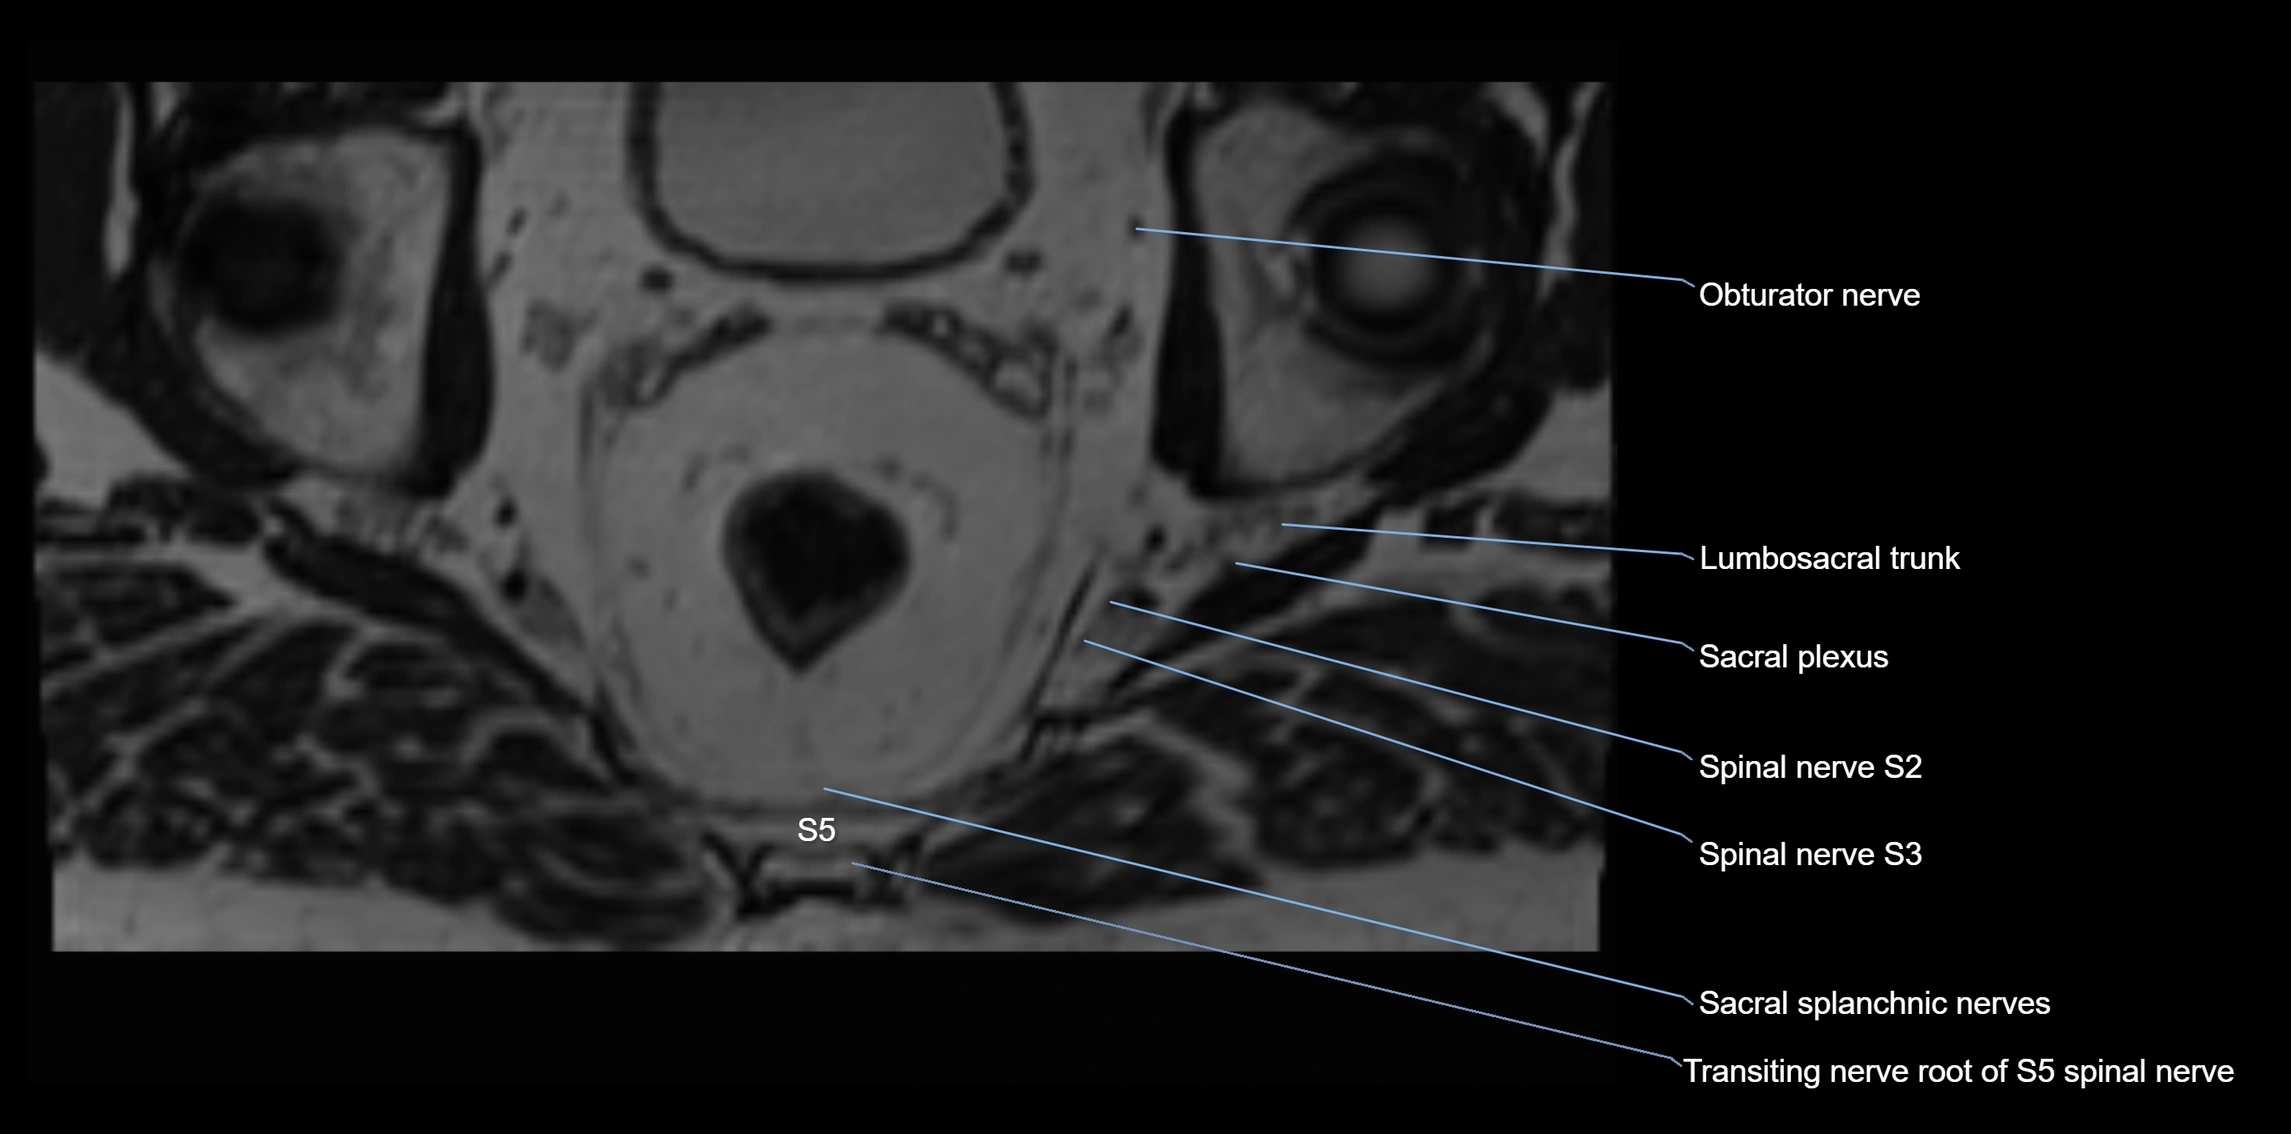

MRI image

image